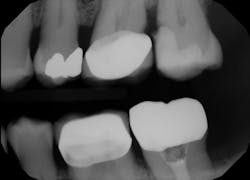

The upper left first molar has recurrent decay at the distal crown margin as well. The open proximal contact may have contributed to the failure of this crown.

The failing composite restoration was removed along with the recurrent decay. A new restoration was placed using VisCalor bulk (figure 2). The flowability of theClinical case no. 2